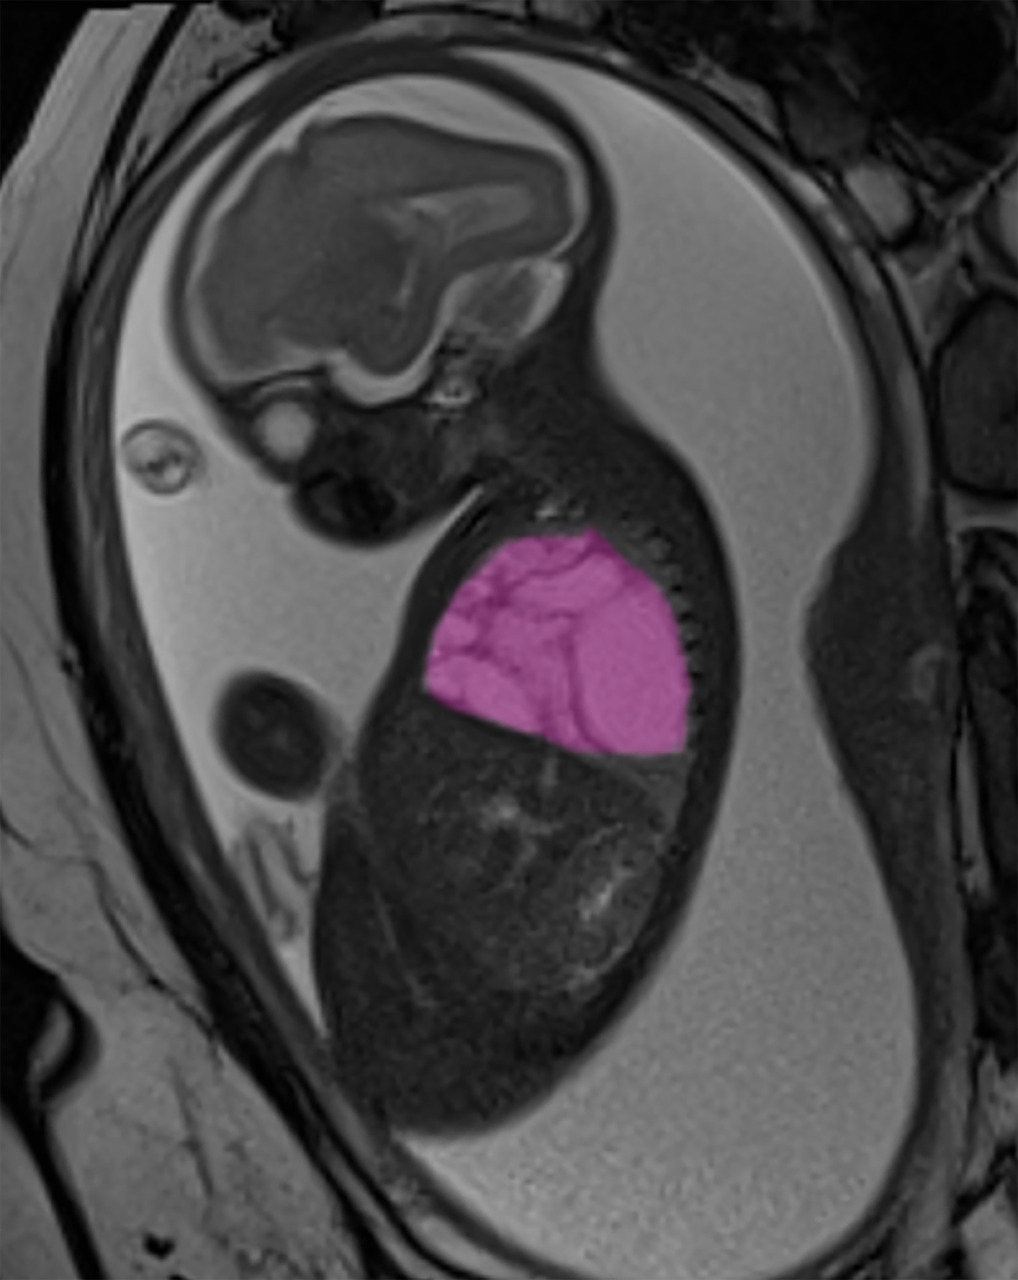

Una cisti polmonare di dimensioni quasi equivalenti all’intero torace metteva in pericolo la vita del piccolo Alessandro (nome di fantasia) già prima della nascita.

Il caso del piccolo è stato gestito dall’équipe di Chirurgia Fetale dell’Ospedale Pediatrico Bambino Gesù, che ha messo in campo una serie di interventi coordinati. Alla 24a settimana di gravidanza, il team ha eseguito un intervento in utero per inserire uno shunt pleuro-amniotico, un sottile drenaggio utile a ridurre la pressione sul cuore del feto e a ripristinare la normale funzionalità cardiaca.